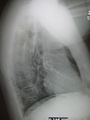

Pneumonia as seen on chest x-ray. A: Normal chest x-ray. B: Abnormal chest x-ray with shadowing from pneumonia in the right lung (white area, left side of image).